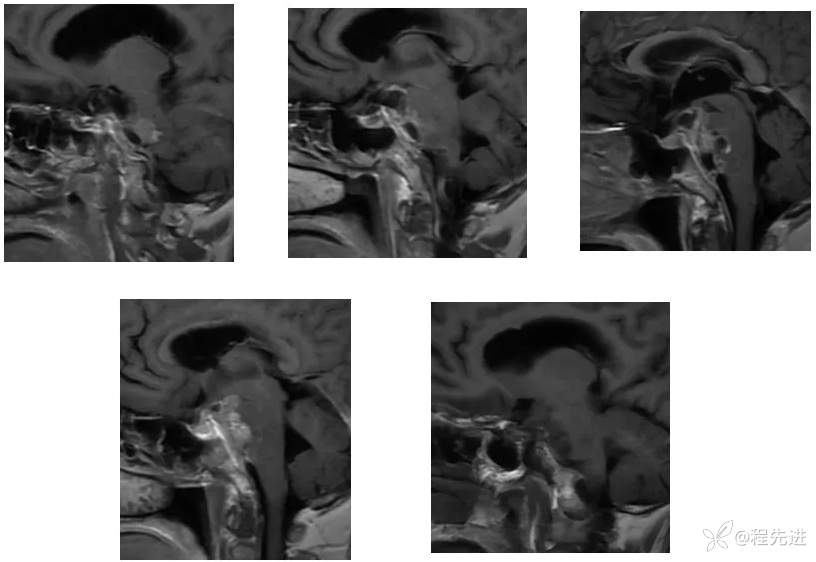

【神经】特别精彩病例|右眼斜视及视力下降7个月,右眼脸下垂3个月,右眼失明1个月

【患者信息】:女,62岁

【现病史及既往史】:右眼斜视及视力下降7个月,右眼脸下垂3个月,右眼失明1个月

【检查】:

查体:生命体征平稳,右眼脸下垂,右眼失明,左眼内收位,外展受限,光反应迟钝,左侧角膜反射减弱,左侧听力下降,左面部痛温觉减弱无吞咽困难,无饮食饮水呛咳,伸舌舌尖左偏。